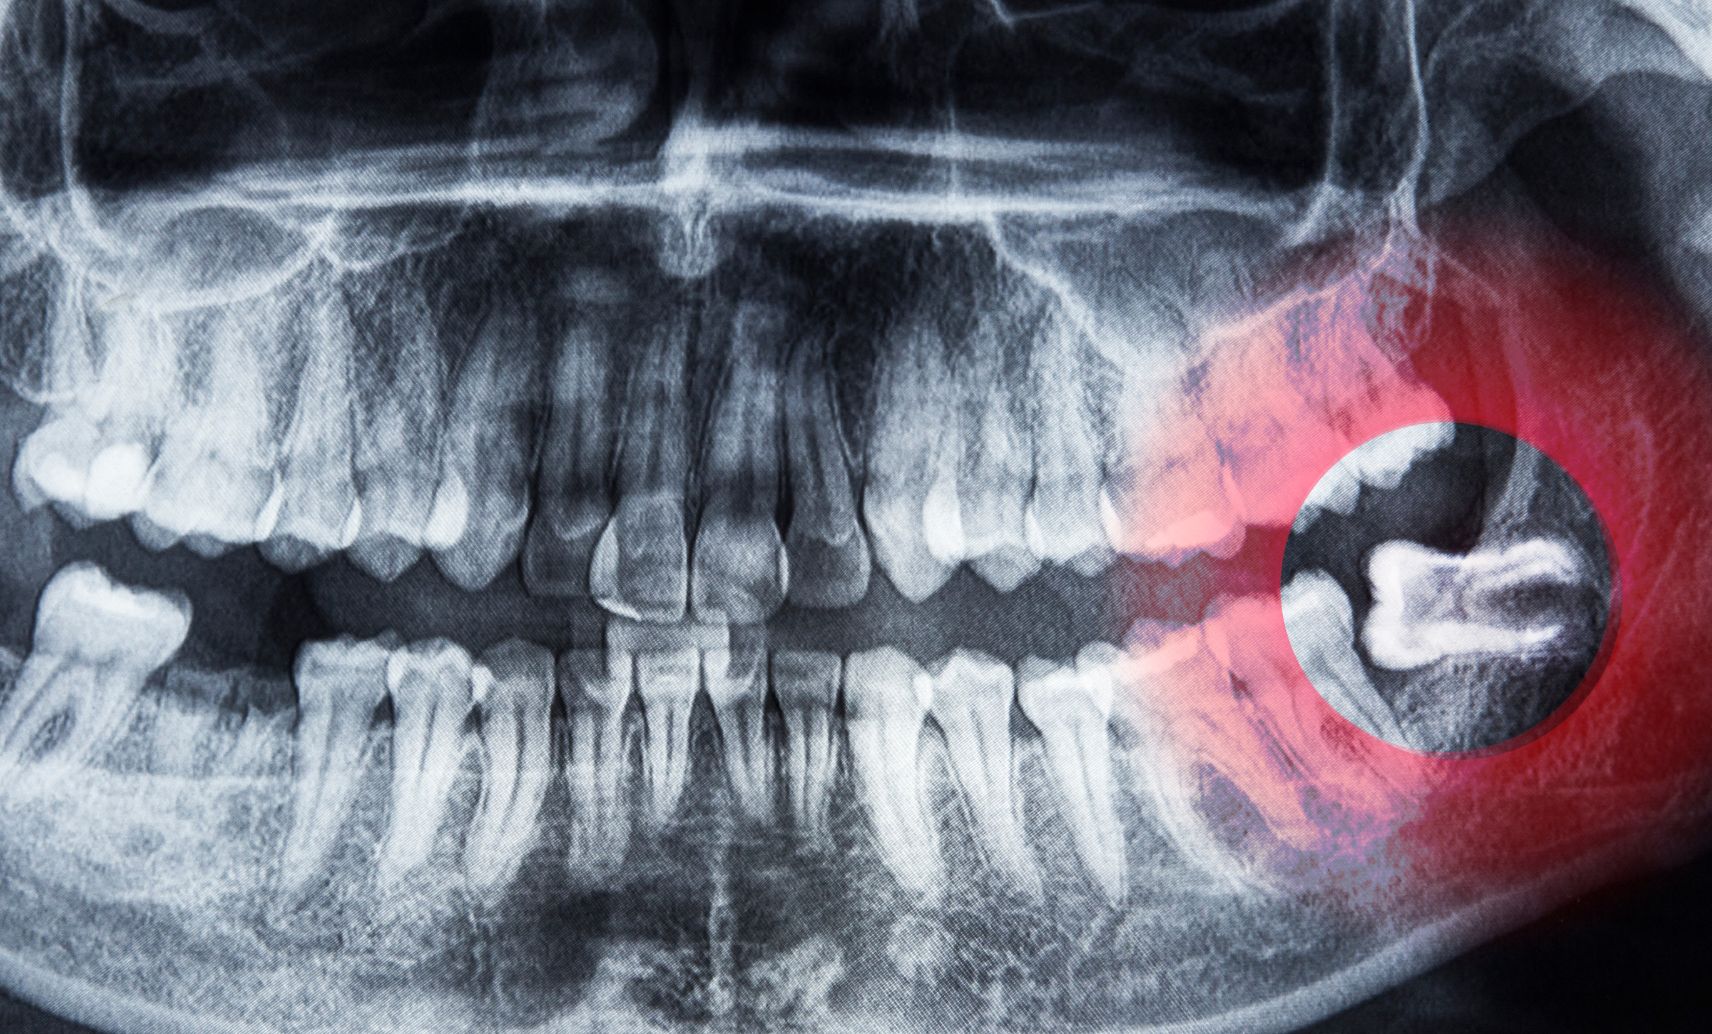

親知らずについて

親知らずとは?

親知らずが痛い原因

親知らずの特徴

親知らずの抜歯基準

親知らずの抜歯手順

親知らず抜歯後の注意点